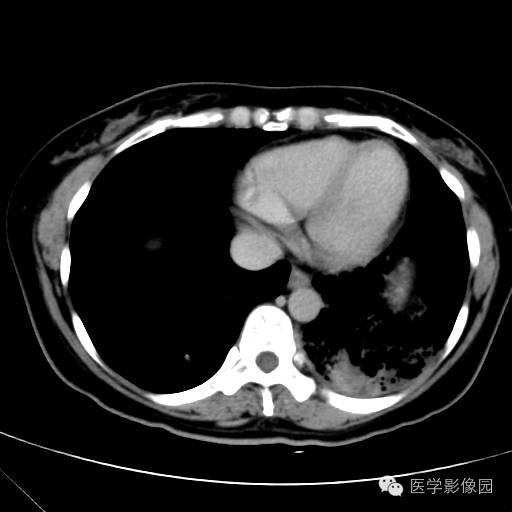

肺叶实变性支气管肺泡癌1例CT影像表现